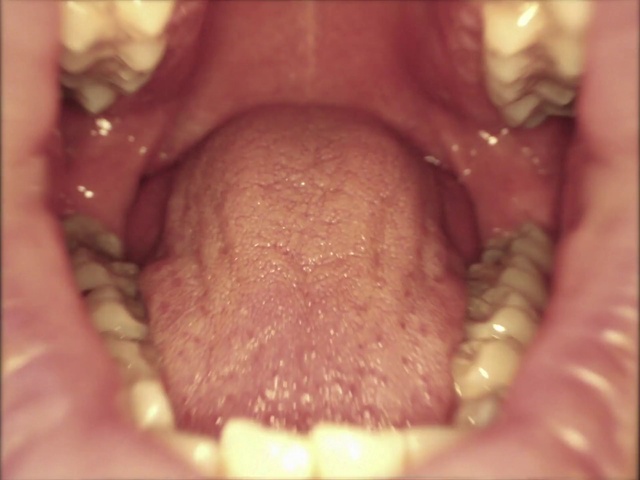

Best Video References: Sore throat

Featured videos selected by a smart neural network algorithm